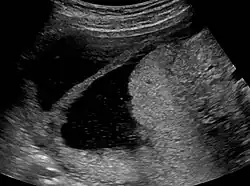

Ultrasound view.

The history of a pregnancy event followed by a D&C leading to secondary amenorrhea or hypomenorrhea is typical. Hysteroscopy is the gold standard for diagnosis.[18] Imaging by sonohysterography or hysterosalpingography will reveal the extent of the scar formation. Ultrasound is not a reliable method of diagnosing Asherman's Syndrome. Hormone studies show normal levels consistent with reproductive function.